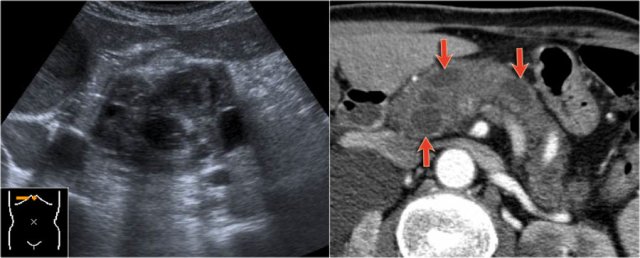

CT-images of a patient with a branch-duct IPMN who choose not to have surgery.

Over time growth of the tumor is seen with dilatation of the main duct indicating malignant transformation.

Sometimes it takes 5-8 years before a transformation is seen.